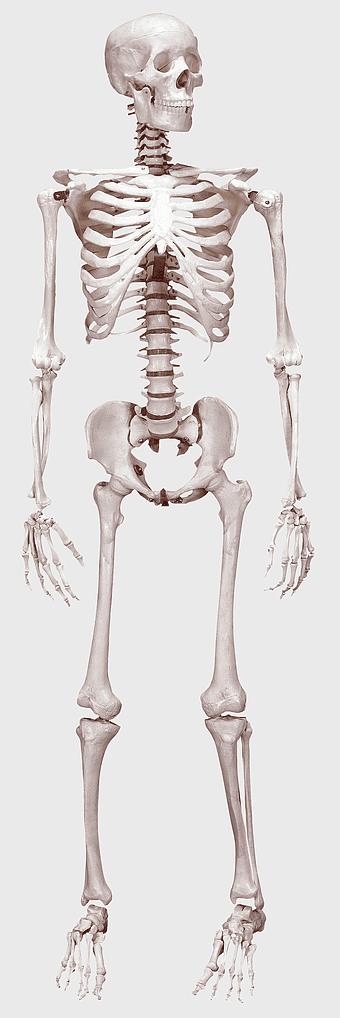

human skeleton illustration, human anatomy bones, skeletal system diagram, human body structure, anatomical reference, medical illustration, educational skeleton image -

Human skeleton, human body anatomy, standing skeleton, bone structure, skeletal system, medical illustration, human anatomy study -

human skeleton, bone structure, nervous system anatomy, joint function, skeletal framework, anatomical illustration, human body composition -

human skeleton illustration, white skeleton decor, rib cage anatomy, vertebral column drawing, skeletal system diagram, medical skeleton art, human bones structure -